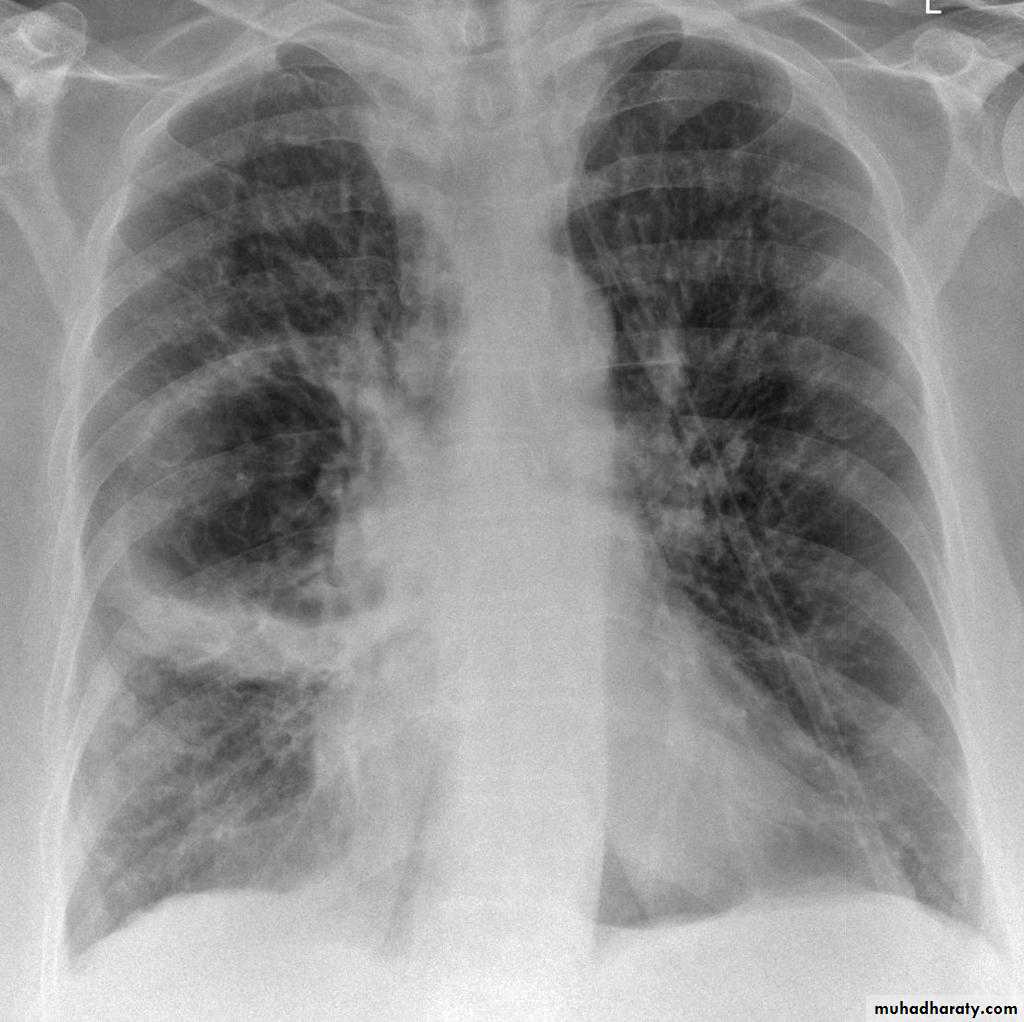

Bronchopneumonia

Bronchopneumonia (also sometimes known as lobular pneumonia 1) is a radiological pattern associated with suppurative peribronchiolar inflammation and subsequent patchy consolidation of one or more secondary lobules of a lung in response to a bacterial pneumonia.Broncho pneumonia

RT ULC

RT U L C

LT L L collapse

RT middle lobe collapse

RT L L collapse

Total lung collapse